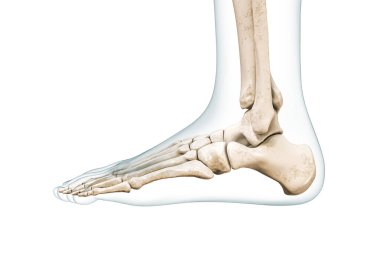

3 boyutlu Talus tarsal kemiği ve beyazı kopyalama alanı ile izole edilmiş. İnsan iskeleti, ayak ve ayak bileği anatomisi, tıbbi diyagram, osteoloji, iskelet sistemi kavramları.

RenkKırmızıbeyazArkaplanRenderGörünümrenkliresimlemeİzole edilmişkenarİnsanSağlıkİlaçSağlık hizmetleriTıbbisiluetBoşlukKemikgövdebiyolojiBilimprofilAyakSistemkemiklerEklemdoğrugörüntü oluşturmaİskeletanatomidiyagramlateraltalustarsusAyak bileğiözetlerkontüriskeletanatomikBoşluğu kopyalaKes şunuosteolojitarsalstarsalBenzer İçerikler